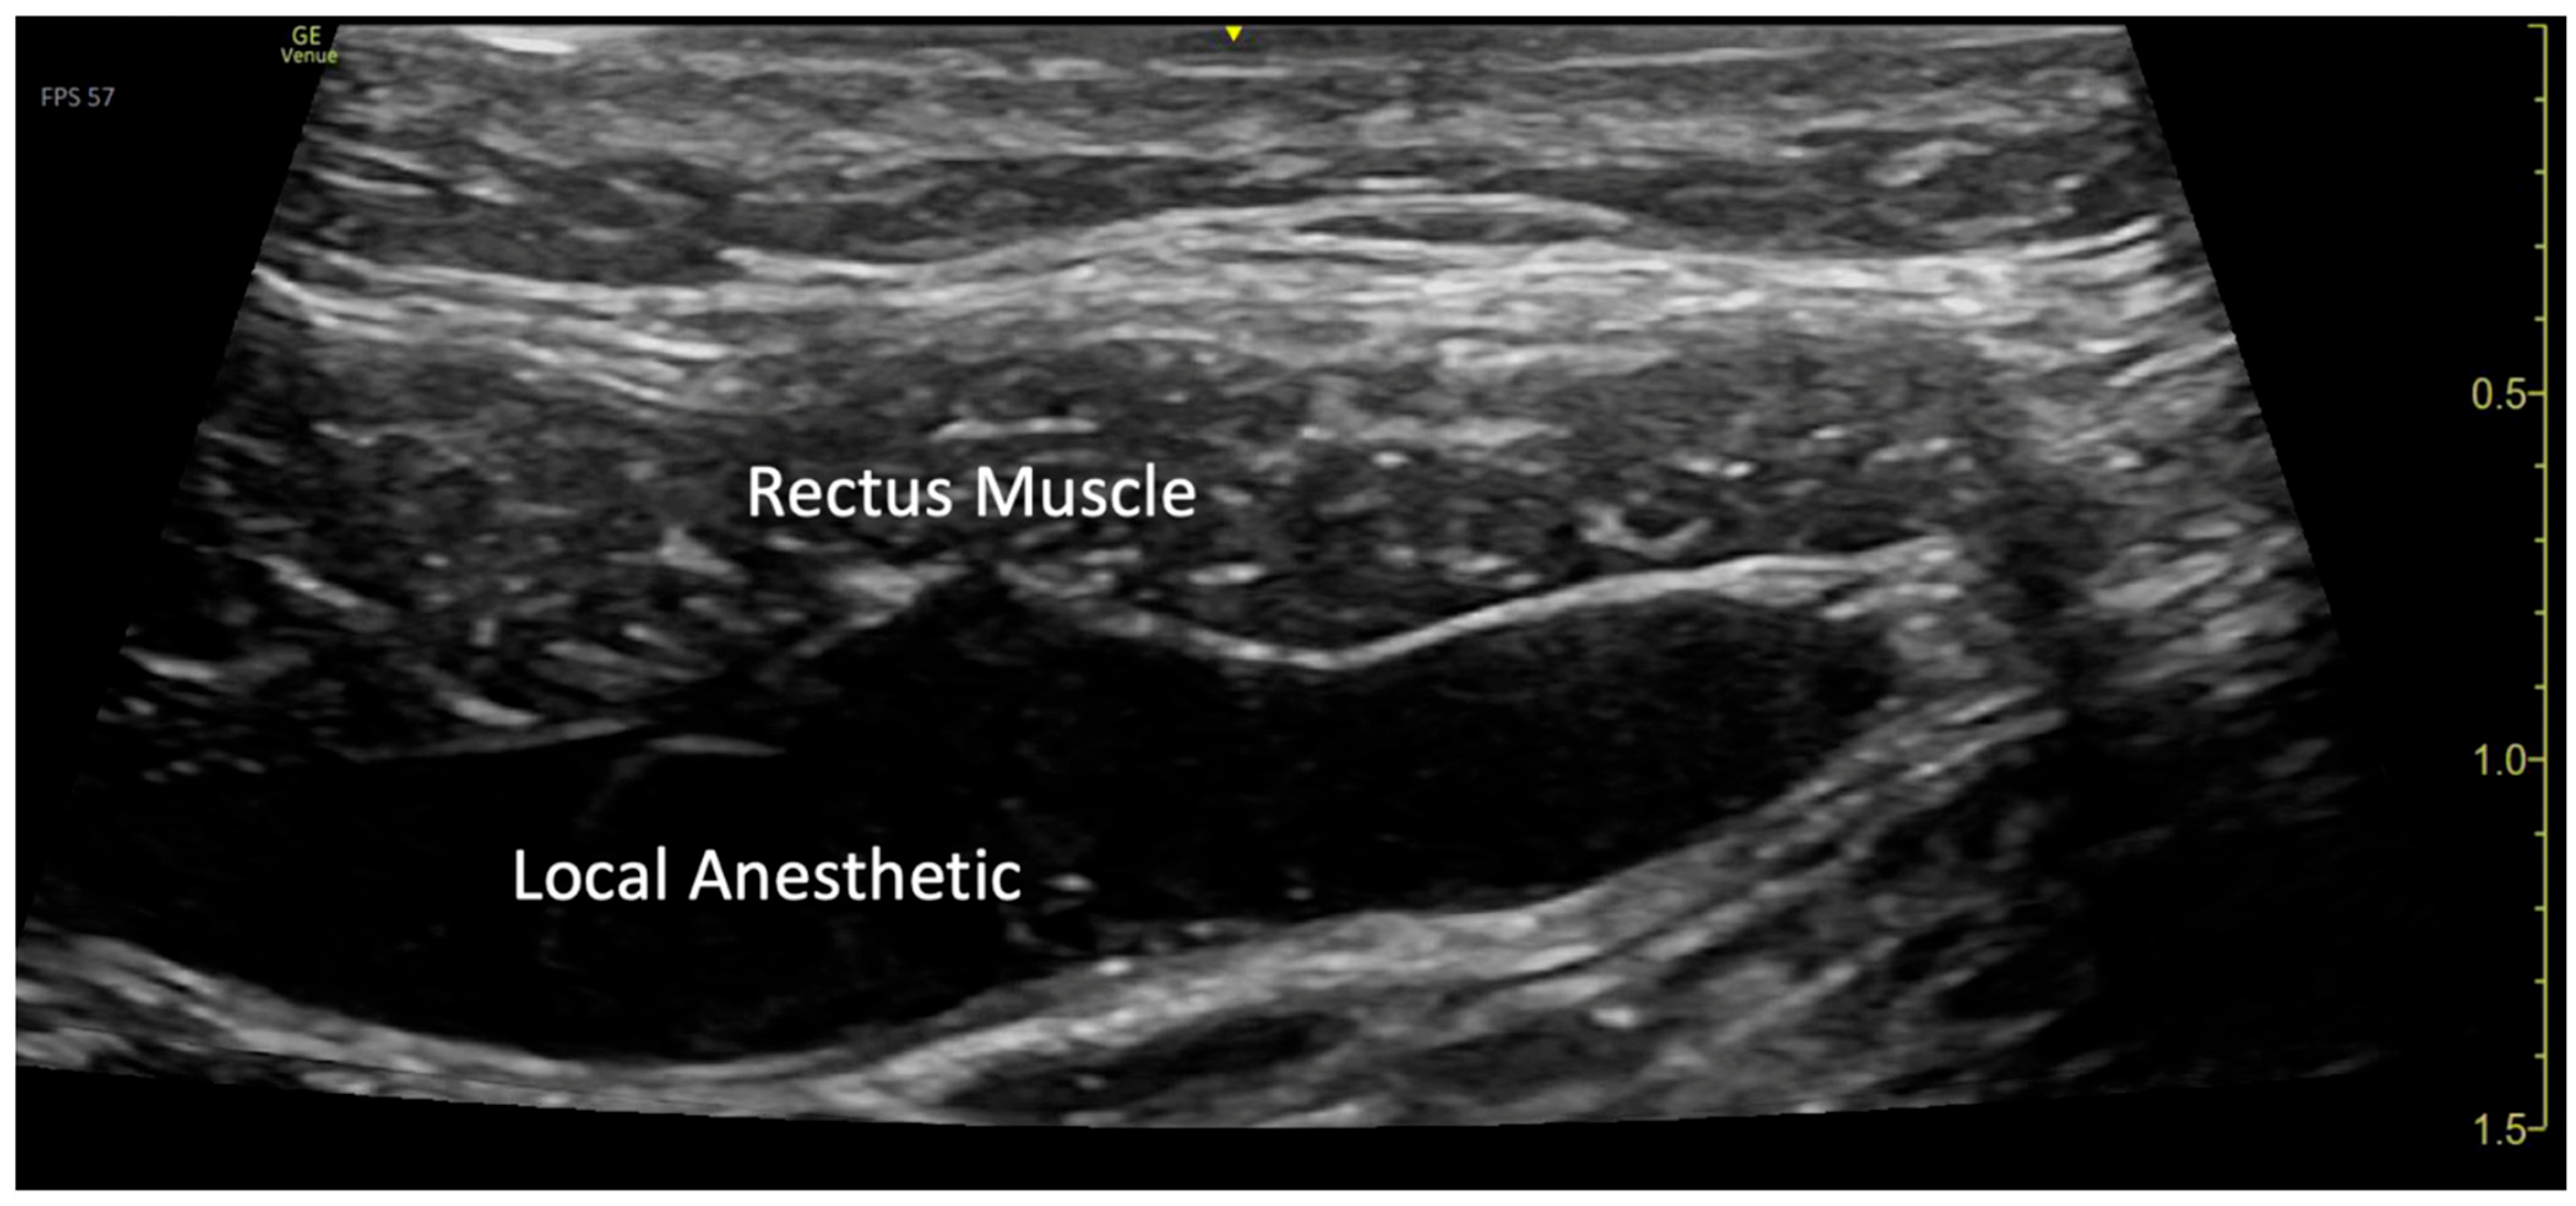

Figure 3.

Visualization of local anesthetic spread under the rectus muscle.

The blocks were performed while the patient was under general anesthesia, before surgery started, and after sterile preparation. A high-frequency linear transducer was positioned at the level of the umbilicus and moved laterally a few centimeters until the lateral border of the rectus muscle was visualized. An echogenic needle, 22-gauge, 50 mm Sono-TAP (Pajunck Medical Inc., Geisingen, Germany) was advanced medially from the lateral edge of the probe; final needle placement was at the lateral border of the rectus muscle, deep to the muscle, yet superficial to the posterior aspect of the rectus sheath, and not pre-peritoneal nor intraabdominal. A few milliliters (mL) of saline solution were injected until the spread of medication was visualized in the correct location (Figure 1), followed by three milliliters (mL) of local anesthetic mixture (liposomal bupivacaine 113.05 mg, bupivacaine 0.25%, 32.5 mg, and dexamethasone PF, 5 mg-total volume 22 mL). This procedure was repeated at the contralateral site. Two more bilateral local anesthetic injections under the rectus muscle were performed at the level of T7 and T12 dermatomes (Figure 2a). A total of six rectus sheath blocks were performed with 22 mL of local anesthetic mixture. After the blocks were performed, medication spread behind the rectus muscle was visualized as a bulge into the space under the rectus sheath muscle from the xiphoid to the pubic symphysis (Figure 3), as described by Visoiu et al. [14], matching the incision performed (Figure 2b) Video S1. The surgery then conducted was an open infrarenal abdominal aortic aneurysm repair with a Hemashift Gold 12 mm graft and a 6 mm limb used for aortic graft to common iliac aneurysm repair. The duration of anesthesia was 374 min, the aortic cross-clamp time was 95 min, and total blood loss for the operation was 500 mL with 180 mL of blood salvage. He also received 4500 units of Heparin during the surgery, which was reversed with 10 mg of protamine. The surgery was uneventful, and intraoperative hemodynamic stability was adequately maintained. The patient was extubated in the operating room.

In our case, we expected that blocks performed at the level of the umbilicus only would not provide adequate analgesia across the entire incision, as noted by Visoiu et al. [14]. Therefore, we performed additional bilateral rectus sheath blocks both above and below the umbilicus. Using ultrasound guidance, we were able to visualize the needle placement and medication spread from the xiphoid to the pubis, ensuring effective pain relief across the entire surgical incision.